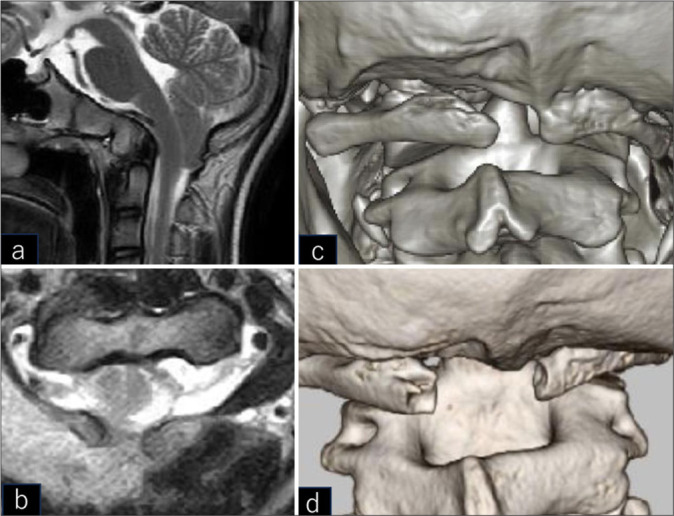

Background: Chiari malformation type 1 (CM1) associated with atlas assimilation (AA) is rarely encountered in children without syringomyelia. Here, a 13-year-old child underwent an original foramen magnum decompression (FMD) for a CM1. Seven years after the index surgery, at age 20, the patient required secondary surgery to address recurrent C1 stenosis attributed to CM1/AA performed without a duraplasty.

Case description: A 13-year-old child originally presented with headaches and CM1 and AA, for which he underwent a FMD without duraplasty. Seven years later, at the age of 20, he developed recurrent C1 stenosis attributed to dorsal bony proliferation of the lamina of the atlas. Following a secondary mini-open exoscopic decompression without duraplasty, he became asymptomatic.